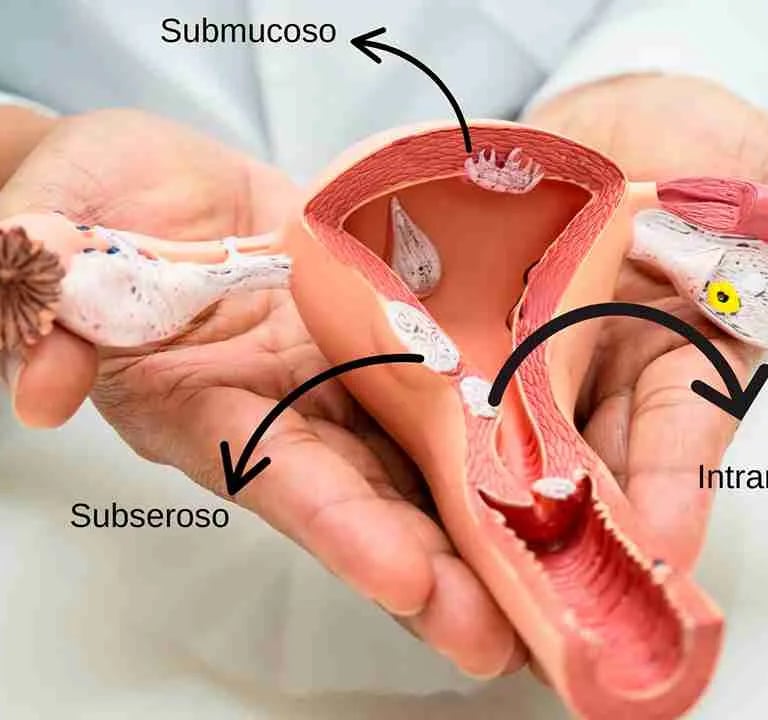

Embolização de mioma uterino

Ablação de miomas uterinos